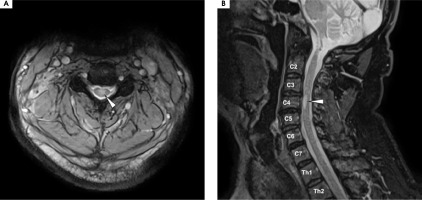

Figure V

Magnetic resonance imaging of the cervical spine, T2 sequence. A) Axial projection: a centrally located hyperintensity is visible in the spine, affecting the gray matter and outlining the anterior and posterior horns, forming the “H sign.” B) A hyperintense lesion is seen occupying the C3-C4 space within the spinal cord. A diagnosis of short-segment transverse myelitis was made at that time